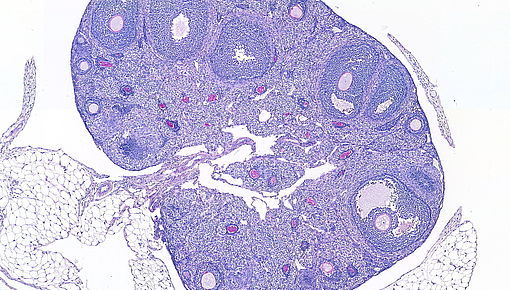

Prenatally in humans and perinatally in mice milestones of ovarian development as critical as the formation of the female’s pool of gametes take place. The gametes and the surrounding specialized stromal cells form the follicles, responsible for ovulation and a main source of sex hormones during the female reproductive life. Importantly, fine-tuned immune responses critically support normal folliculogenesis, ovulation and corpus luteum formation and regression. For example, ovarian macrophages regulate discrete remodelling and vascularization processes that ensure the access of follicles to nutrients and steroid substrates and the egress of hormones into the circulation.